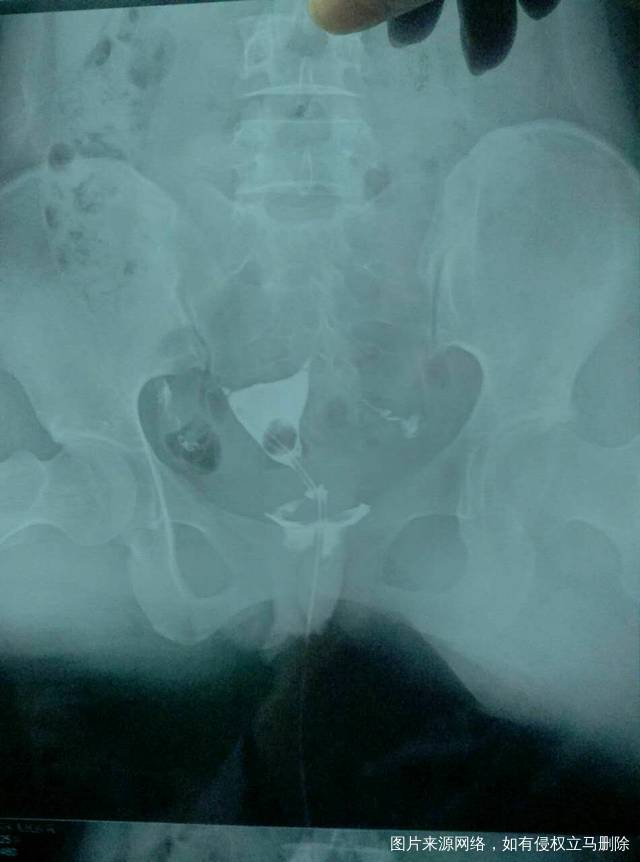

输卵管造影结果,请各位医生帮忙看看 有什么治疗方法?谢谢!

今天做的输卵管造影,请各位医生说说我该怎么治疗。